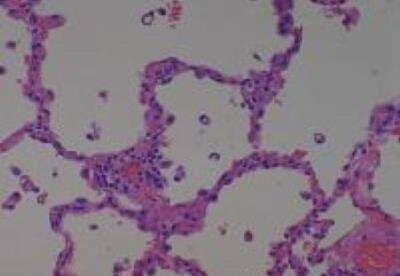

Hematoxylin & Eosin Stain: Human Common Tissue MicroArray (Normal Adjacent) [NBP2-30215] - 01. Stomach